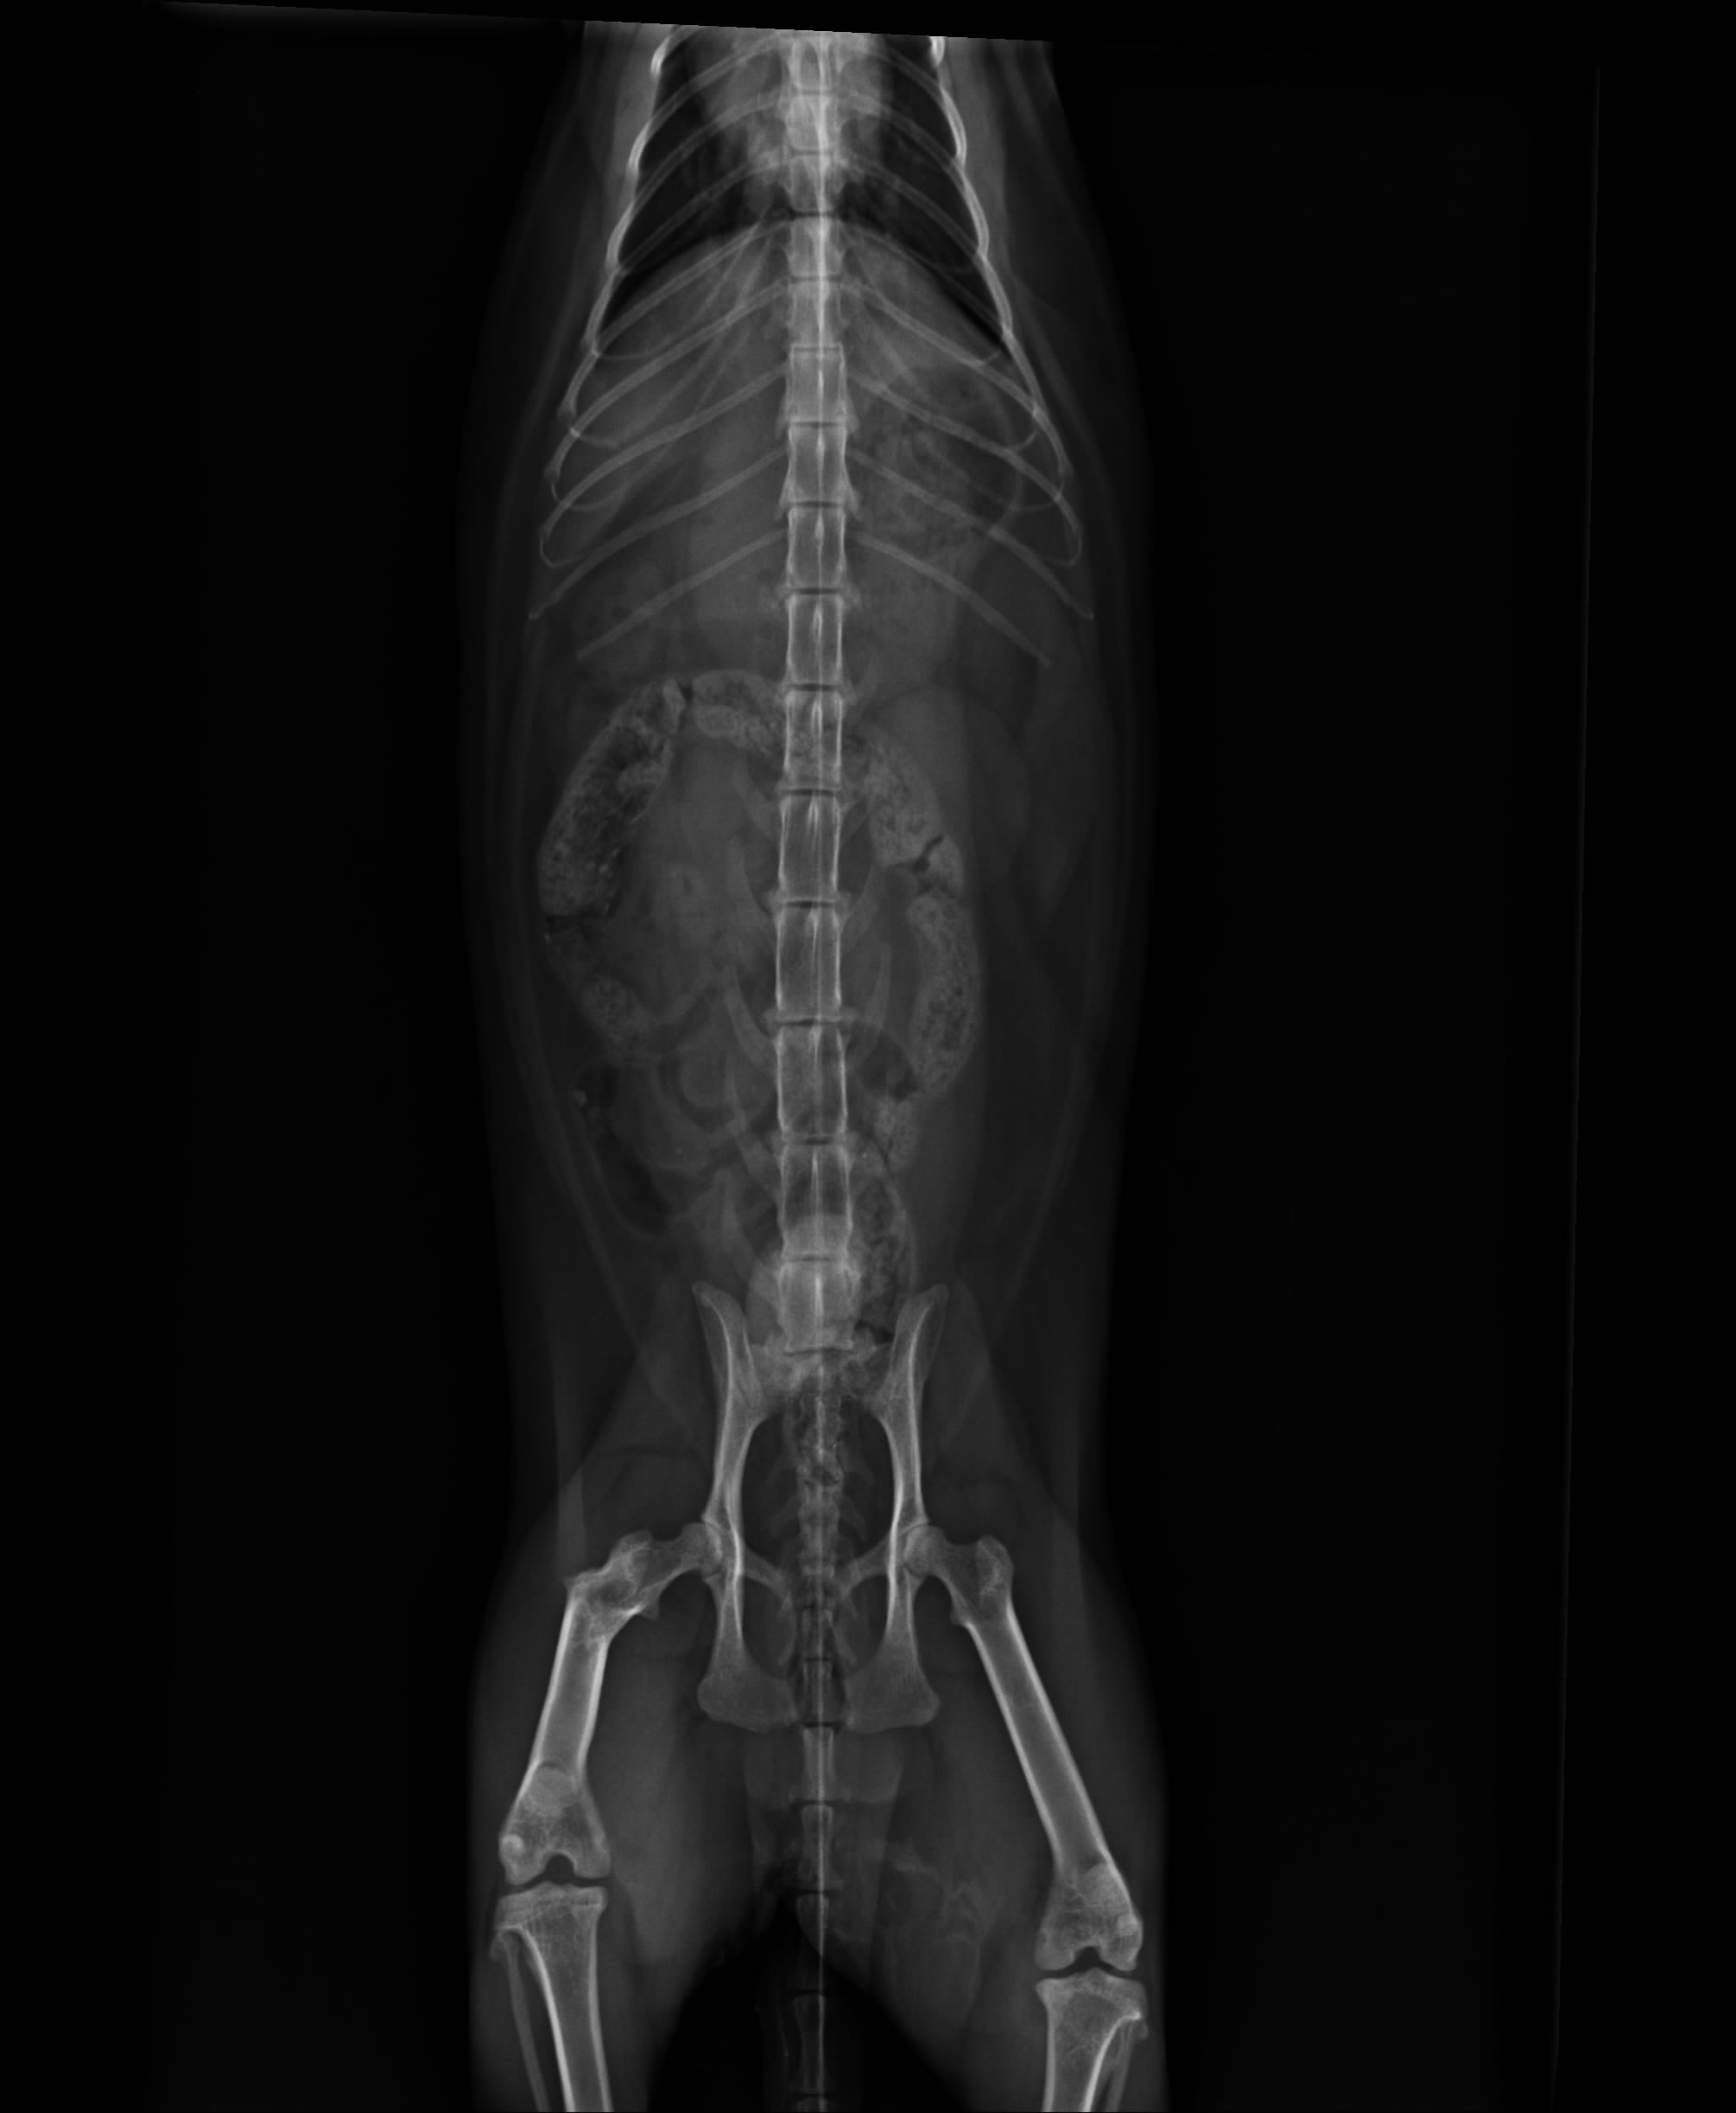

在醫生細心檢查後.尿道口膿樣分泌物經X-ray檢查發現有一直徑3cm結石,並手術取出,目前貓咪的復原狀況良好,為節省住院開消,貓咪已由志工接回照顧,待傷口與體力恢復至最佳狀態,會再放回原地.

4.X光檢查 400